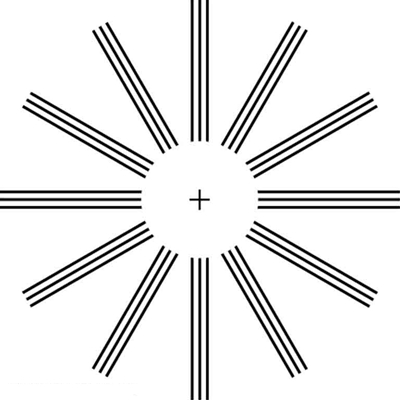

散光圖片

A:判斷自己有沒有散光,最簡單的方法是使用散光表來測試。散光表是一種簡單、方便的方法,但是它的準確度不是特別精確。在配鏡的情況下一般再用裂隙法,或者是交叉圓柱鏡法來精調散光的度數。散光表在網上可以看到,它類似於鐘錶的盤面,有12個數字。各個鏡線……